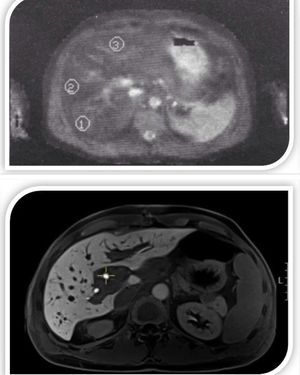

Early liver MRI scan from the 1986 (Richards M.A. et al.) (upper image) and nowadays high resolution 3D T1-w Spoiled GRE/VIBE (lower image)!